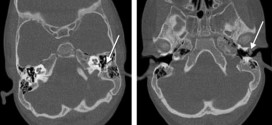

CARCINOMA EPIDERMOIDE DE OÍDO MEDIO

El carcinoma epidermoide de oído medio. Los carcinomas epidermoide de oído medio son raros 1-2/1000000/año. CAE/oído medio: 10/1. Tipo histológico más frecuente Ca epidermoide (70%), seguido del Ca basocelular. Durante los primeros años de vida de una persona, las células normales se dividen más rápidamente para permitir el crecimiento. El cuerpo está compuesto por billones de células vivas. Las células …